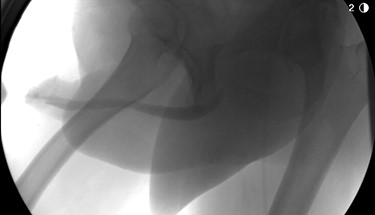

The patient underwent further evaluation with imaging including renal ultrasound, which was normal. Flexible cystourethroscopy demonstrated a circumferential urethral mass concerning for urothelial carcinoma (Fig. 1), which was biopsied with histopathology negative for urothelial carcinoma but positive for amyloid protein deposition. Examination of the external genitalia was unremarkable and there was no palpable induration along the ventral penile shaft. Systemic workup for additional manifestations of amyloidosis was negative. Imaging with retrograde urethrography (RUG) demonstrated an ~2 cm segment of urethral stenosis in the penile urethra (Fig. 2).

RUG demonstrating focal urethral stenosis of the penile urethra during preoperative investigation.